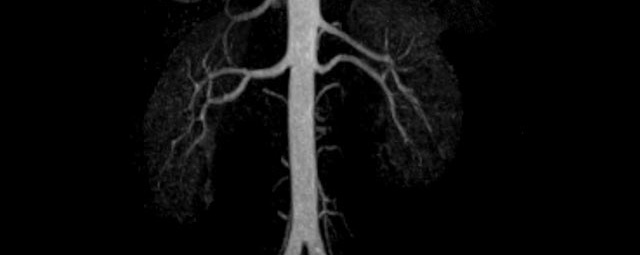

• Bauchgefäße

• Erfassung und Verlaufskontrolle bei arteriellen Aneurysmen (Aussackungen der Arterien), vor allem der Bauchaorta

• Darstellung von Gefäßengen an Nierenarterien, Baucharterien und Becken-/Beinarterien

MR-Angiografie (MRA)

• MR-Angiographie mit Kontrastmittel

• Erfassung arterieller und venöser Gefäße/Bypässe aller Körperregionen mit 3D-Rekonstruktion